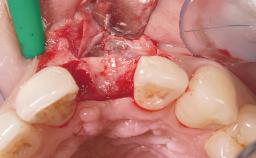

A 42-year-old female patient was referred to our clinic at the School of Dentistry of the University of São Paulo in November 2004, presenting a deficient restoration in the upper left central incisor. The clinical examination revealed no gingival retraction or any signs of gingival inflammation and, therefore, previous periodontal treatment was not considered. The patient presented a high lip line at full smile and a thin tissue biotype. This combination characterized a high-risk situation from an anatomic point of view, which required careful preoperative planning and cautious surgical execution.

Loading Protocol Immediate

Provisional Implant-Supported Prosthesis Prosthodontic margin < 3 mm apical to mucosal margin Prosthodontic margin < 3 mm apical to mucosal margin